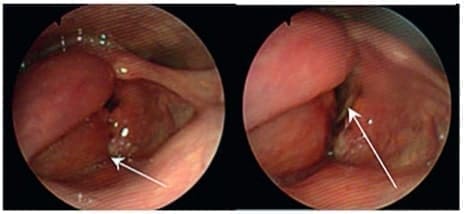

Se realizó un esofagograma que no mostró fugas o lesiones fistulosas (figura 6), y una nasofibrolaringoscopia que documentó un hematoma hemilaríngeo derecho (figura 7); este examen se repitió a las 24 horas sin observar cambios respecto al estudio inicial.

Figura 7. Manejo Conservador de Lesión Aerodigestiva – Nasofibrolaringoscopia observando un hematoma en la hemi-laringe derecha (flecha corta) que obstruía el 50 % de la luz glótica (flecha larga) impidiendo avanzar el naso-fibro-laringoscopio. Fuente: los autores.

La endoscopia de vías digestivas altas informó la presencia de un hematoma que comprometía la pared lateral de la tráquea, sin embargo, mediante un paso fácil del endoscopio por el cricofaríngeo, no se visualizaron lesiones en el esófago.